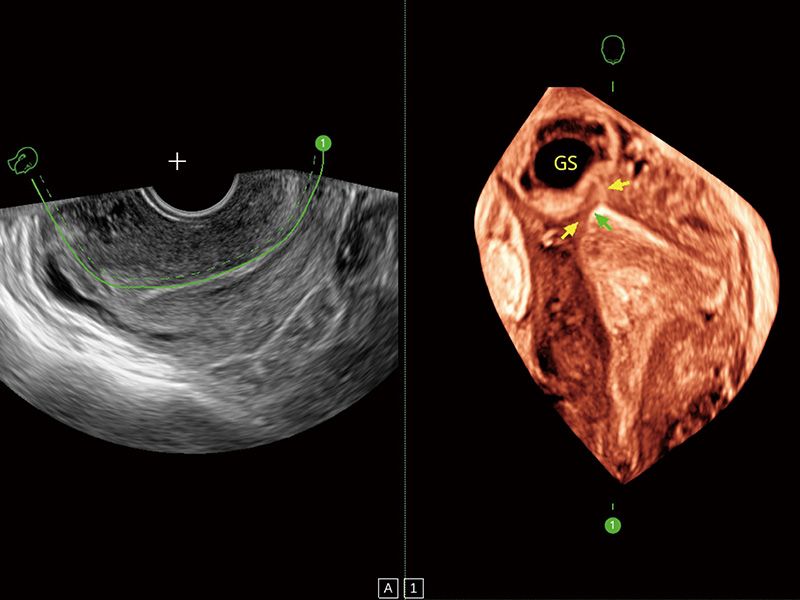

“生育问题”即关系民族复兴,也关系亿万家庭的幸福。随着婚育年龄推迟、社会压力增加等因素,越来越多人群也面临着“生不出、生不好”的问题。辅助生殖作为治疗不孕不育最有效的方法之一,也逐渐成为育儿新希望。而超声检查能为生殖需求人群的初诊评估提供宝贵的信息。 P20 Elite是百老汇电子游戏官网匠心打造的一款生殖应用型彩超。她继承百老汇电子游戏官网高端极光平台,突破性地将多款新型芯片及硬件模块进行整合,均衡了高端系统性能与小巧灵动机身。P20 Elite卓越的图像质量搭载专科探头,旨在为您提供全面的辅助生殖解决方案。

P20 Elite配备了丰富的生殖探头群和临床应用功能,在卵泡监测、穿刺取卵、胚胎移植、妊娠确认等领域,为生殖需求人群提供了新的临床机会,重新定义高端超声如何应用于生殖健康检查。